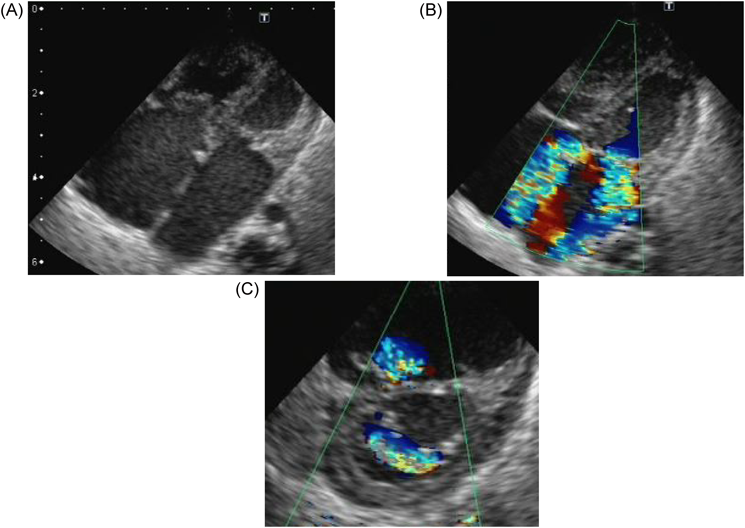

胎児心臓超音波検査ではCTAR47%,心横径ϕ35.6 mm,心拍数148 bpm,四腔は著明に拡大,右室壁の肥大を認め,僧帽弁輪径11.2 mm, MR重度,三尖弁輪径10.4 mm, TR重度,左室駆出率(Left ventricular ejection fraction; LVEF)50%であった(Fig. 1).肺動脈弁の狭窄はなく,動脈管,卵円孔の閉鎖は認めなかった.また,供血児はCTAR29%,心横径28.0 mmと週数相当であり房室弁逆流を認めなかった.在胎週数が早く,FLP後のため房室弁逆流が改善する可能性に期待し経過観察とした.分娩時期に関しては,供血児に異常がないため供血児を優先して判断する方針とした.経過中,胎児のnon-stress test(NST)では両児ともにreassuring patternで,臍帯血流の途絶が見られず観察を続けることができた.出生前の弁輪径とCTARの推移は在胎28週1日,僧帽弁輪径12.4 mm,三尖弁輪径14.1 mm.在胎29週5日,僧帽弁輪径12.9 mm,三尖弁輪径13.3 mmで在胎32週1日,僧帽弁輪径12.3 mm,三尖弁輪径13.6 mm, CTAR47%であり,重度のMR, TRは持続した.在胎32週4日,前期破水のため帝王切開とした.

Fig. 1 Fetal echocardiogram of the recipient at 27 weeks’ gestational age

(A) shows left and right atrial enlargement. (B) shows severe mitral and tricuspid regurgitation.

Fig. 3 Electrocardiogram at birth shows biventricular hypertrophy and biatrial overload

心臓超音波検査:僧帽弁輪径10.8 mm,僧帽弁に肥厚(A1–A3, P2)と前尖(A2)に軽度の逸脱あり,MR重度でA1からA3まで幅広く認め左心房後壁へ向かう,乳頭筋は2つ認め腱索に断裂なし,左室流入血流E/A=0.86/1.0 m/s,三尖弁輪径12.7 mm, TR重度で接合不全を認め中央部から後方かつ中隔側へ向かう(Fig. 4),推定右室圧66.0 mmHg, LVEF 57.8%,左室拡張末期径(left ventricular end-diastolic dimension; LVDd)16.5 mm,左室壁厚2.9 mm,動脈管径1.5 mmで左右短絡,冠動脈起始異常なし.

Pediatric Cardiology and Cardiac Surgery 33(3): 215-220 (2017)

Fig. 4 Echocardiogram of the recipient baby at birth

(A) shows left and right atrial enlargement. (B) and (C) show severe mitral regurgitation and tricuspid regurgitation.